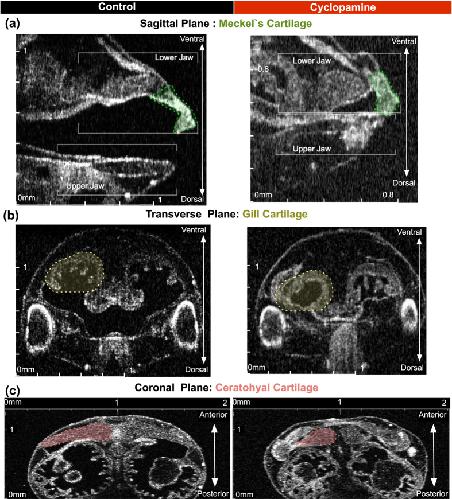

Figure 5. Quantitative neural crest defects in Xenopus with cyclopamine treatment.(a/aâ²âc/câ²) Stage 46 control tadpole compared to cyclopamine (2.5âmg) treated tadpoles. The tadpole is positioned on the ventral side up, and the OCT imaging plane scrolled along the z-axis until the largest mid-lateral portion of the cartilages is visualized. We acquired a set of 3D data. On these coronal sections a line between two points traveling along the mid-corpus of the Meckelâs and ceratohyalcartilage is measured. Then the largest middle and lateral borders along the corpus of the most anteriorgill are marked, and the midline length is measured. Quantitative analysis demonstrated reduction in length and area in treated tadpoles on the coronal plane. L: left, (Mann-Whitney test; pâ<â0.05) (*pâ<â0.05/**pâ<â0.01/****pâ<â0.0001) (Bars represent mean with 95% confidence interval).